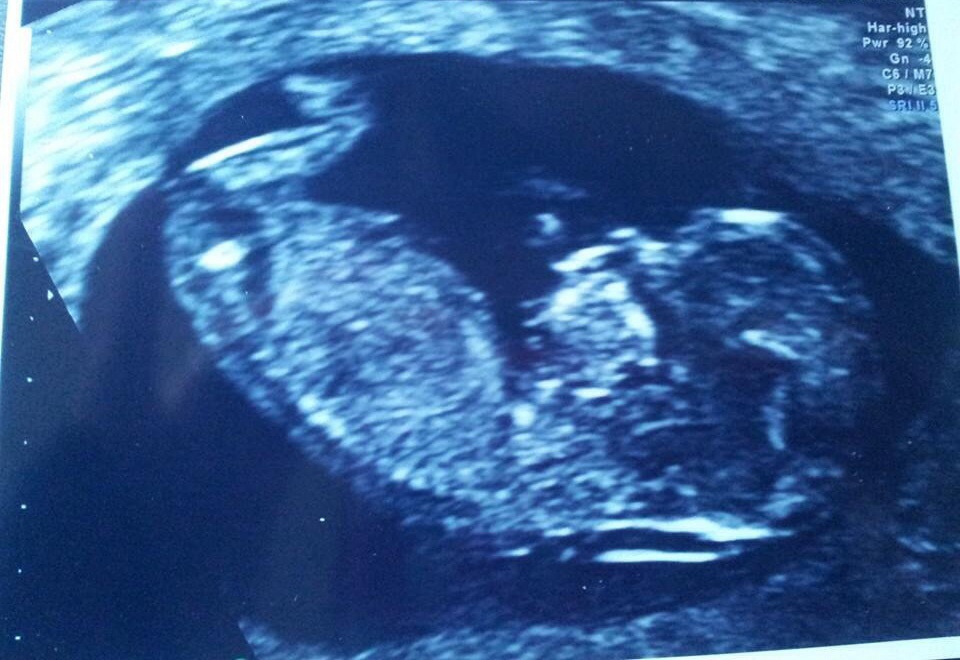

Any theories welcome we're dying to know a.s.a.p!Attachment 16222

Sorry, baby is hiding the nub well :-/ Hope you find out soon :)

Aw thanks anyway :-) anyone else who is good at skull theory? X

No clues! sorry, I cant tell by skull, congrats x